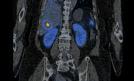

Po raz pierwszy w województwie zachodniopomorskim zastosowano terapię radioizotopową z wykorzystaniem radiofarmaceutyku 177Lu Lutathera u pacjentki z rozpoznaniem atypowego rakowiaka płuc z obecnością przerzutów. Zrobiono to 11 maja w Zakładzie Medycyny...